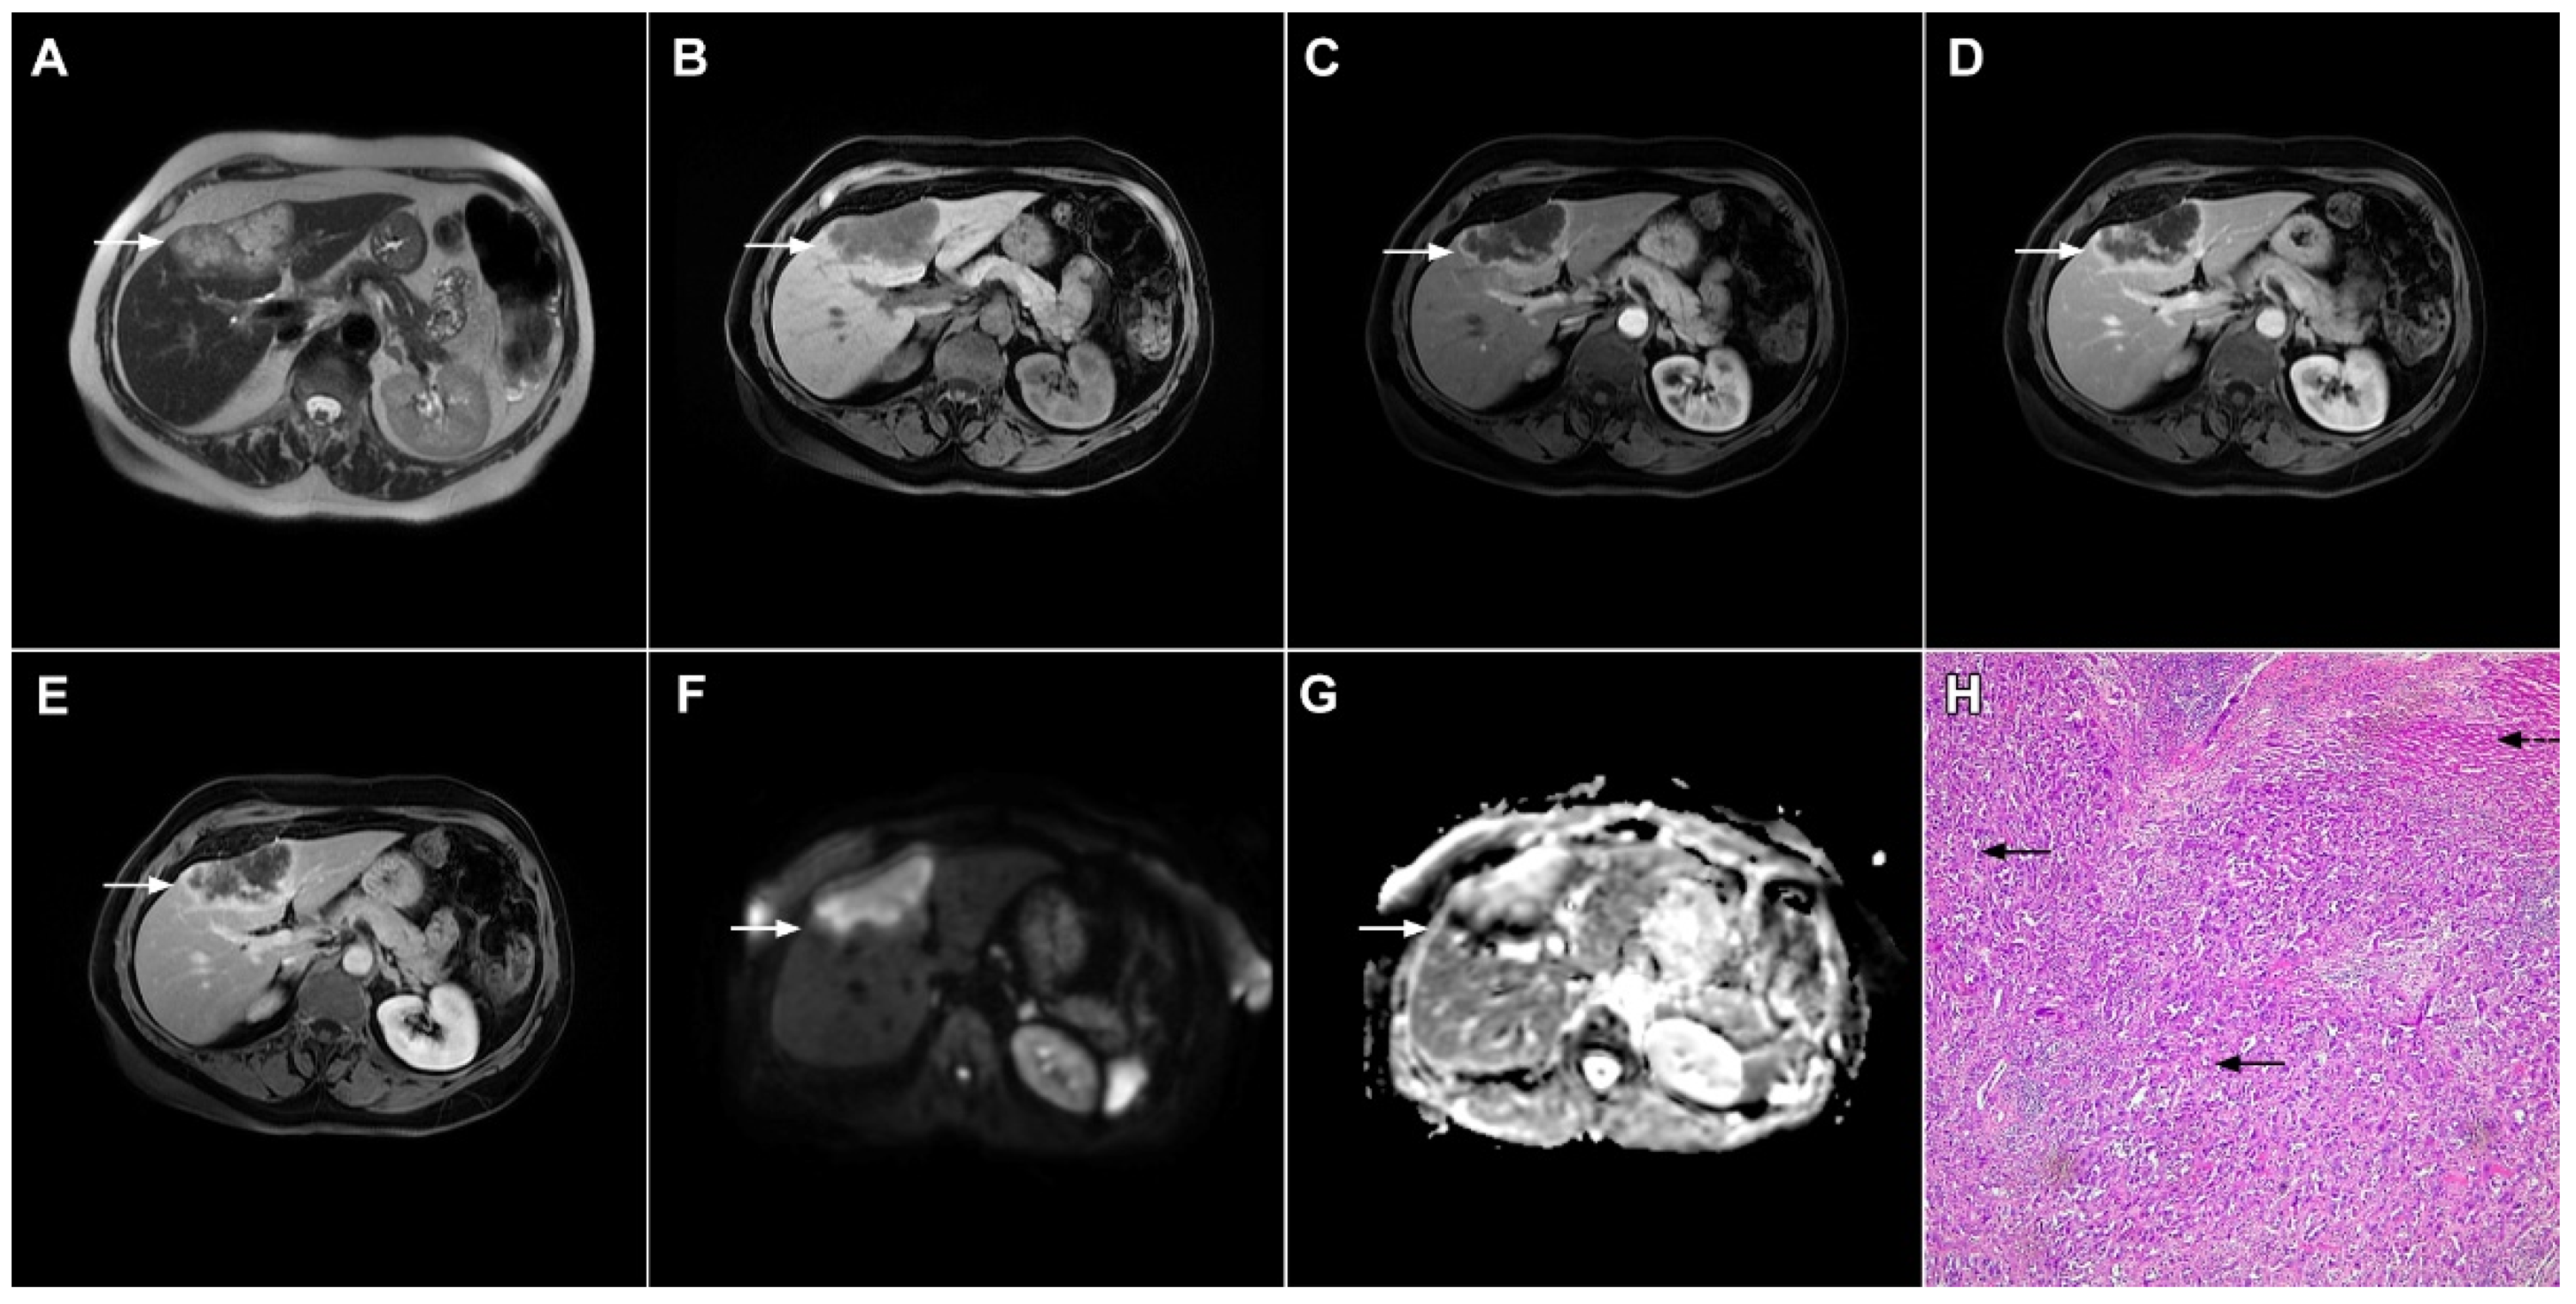

Figure 7.

Mucin-rich mass-forming cholangiocarcinoma in a 78-year-old woman. The axial T2-weighted image (A) shows the lobulated hyperintense lesion (arrow) located in the subcapsular region of liver segment IVB, which is associated with capsular retraction. On the plain T1-weighted image (B) the lesion (arrow) is hypointense. In the arterial phase (C), ring enhancement can be seen with slight “ragged” central enhancement in the portal venous (D) and delayed phase (E). On DWI, diffusion restriction is noted on the periphery of the lesion (arrow) while no restriction is seen in the central part of the tumor (F). Corresponding ADC map showing targetoid appearance of the lesion is shown on (G). Hematoxylin and eosin (H&E) staining (H) showed cholangiocarcinoma (arrows) adjacent to normal liver parenchyma (dashed arrow); original magnification ×40.